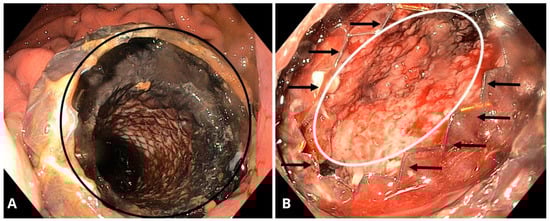

6. Endoscopic Drainage of PPCs

6.4. Stents in Endoscopic Drainage of PPCs

6.8. Lumen-Apposing Metal Stents (LAMSs)

6.9. LAMS- and DPPS-Related Complications

6.12. Endoscopic Ultrasound (EUS)